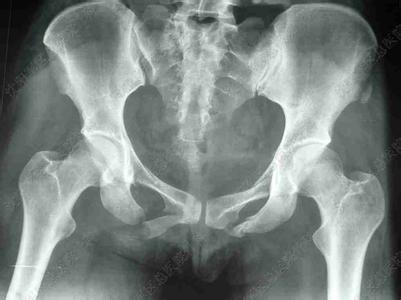

骨盆骨折的常见并发症。不同的原因会导致骨盆骨折,骨盆骨折后也会常常出现一些并发症,主要有以下五种:

骨盆骨折的常见并发症